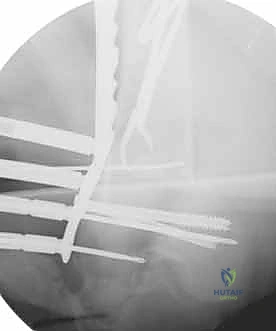

المرحلة الثالثة: إرجاع العظم (Reduction)

هذه هي الخطوة الأكثر أهمية. يقوم الدكتور هطيف بإعادة القطع العظمية المكسورة إلى مكانها التشريحي الأصلي. إذا كان الكسر ممتداً داخل المفصل، يتم تثبيت السطح المفصلي أولاً باستخدام مسامير دقيقة لضمان سطح أملس يمنع الاحتكاك والخشونة مستقبلاً.

المرحلة الرابعة: التثبيت النهائي بالشرائح والمسامير (Fixation)

يتم استخدام "شرائح الإغلاق التشريحية" (Anatomical Locking Plates) المصنوعة من التيتانيوم عالي الجودة. هذه الشرائح مصممة خصيصاً لتأخذ شكل الجزء السفلي من عظم الفخذ. يتم تمرير الشريحة أسفل العضلات وتثبيتها بمسامير تغلق داخل الشريحة نفسها (Locking Screws)، مما يوفر ثباتاً ميكانيكياً هائلاً، حتى في حالات العظام الهشة.